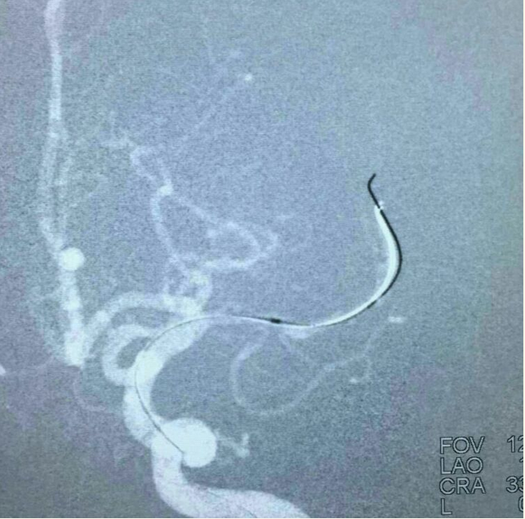

支架(Solitaire 4.0*20)到位尚未打开: